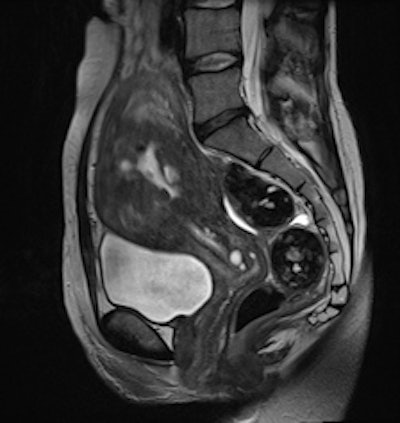

Cervical carcinoma: The uterine zonal anatomy and bladder wall as well as the bowel loops are more sharply delineated on the BLADE image (right); however, SNR and CNR are higher on the conventional T2-weighted image (left)."Indeed, conventional T2-weighted TSE provided a significantly better visibility of free pelvic fluid or cystic structures (i.e., a relatively higher effective T2 weighting) in numerous cases," the researchers noted.

Adenomyosis and intramural leiomyomas: The intramural uterine changes, cervical structures, and bladder wall are more sharply delineated on the BLADE sequence (right); however, SNR and CNR are higher on the conventional T2-weighted image (left). There are also fewer motion artifacts in the surrounding tissue on the BLADE image."From a diagnostic point of view, the distinctive MRI properties of cystic structures are of primary importance when performing female pelvic imaging," they added. "Additional use of contrast showing enhancement of solid tumor components besides including conventional non-Cartesian sampled T1- and T2-weighted images into the protocol are advocated to facilitate the diagnosis and to avoid pitfalls."